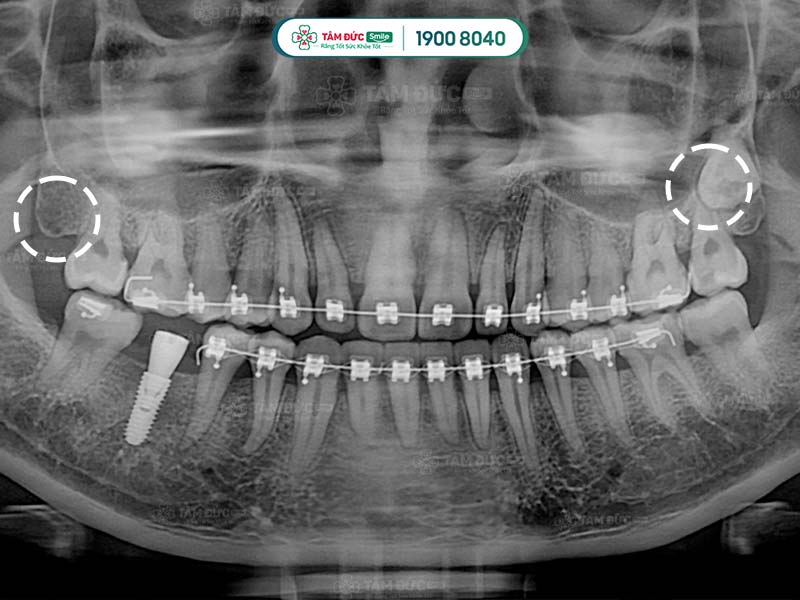

1.4. Bị viêm nướu răng có mủ do mọc răng khôn

Răng khôn là những chiếc răng mọc sau cùng, khi xương hàm và nướu đã phát triển ổn định. Không có đủ khoảng trống nên chúng thường sẽ mọc ngầm, mọc lệch hoặc xâm lấn với những chiếc răng khác trên hàm. Điều này có thể làm Quý khách cảm thấy đau nhức khó chịu và phải nhổ bỏ răng. Mặt khác, đau răng khôn còn ảnh hưởng tới sức khỏe răng miệng, trong số đó có bệnh lý viêm nướu răng có mủ.

Răng khôn mọc ngang làm chân răng kế cận bị tổn thương, gây ra viêm nướu có mủ